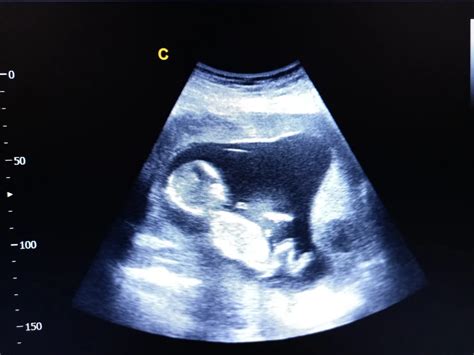

Pe parcursul acestor patru săptămâni, fătul aflat în continuă creştere îşi schimbă mult aspectul, astfel că, în săptămâna a 10-a, va începe să semene cu o fiinţă umană. În săptămâna a 6-a, apar mugurii viitoarelor mâini şi picioare. Capul continuă să crească mai repede decât orice parte a corpului pentru a găzdui creierul aflat în continuă dezvoltare. Copilul are o lungime de 12 mm (0,5 inchi), iar bătăile inimii se pot vedea la ecograf. Ochii şi urechile copilului se dezvoltă repede; până la sfârşitul săptămânii 8, ochii au deja o anumită culoare. Cutele pielii care alcătuiesc mugurii viitoarelor membre încep să formeze cartilaj, din care se vor dezvolta mai târziu oasele. Poţi vedea mişcările copilului tău la ecograf, dar deocamdată nu le simţi.

La sfârşitul săptămânii 10, copilul are o lungime de 22 mm (0,9 inchi). Poţi să-i distingi ochii, care deocamdată stau ascunşi sub pleoapele închise şi care nu-şi vor intra în rol decât ceva mai târziu, în al doilea trimestru, când se formează sistemul nervos. Inima, cu cele patru compartimente definitive ale ei, s-a format deja; inima bate de 160 de ori pe minut. Faţa copilului este formată complet; ficatul, stomacul şi splina sunt la locul lor. Poţi să-i vezi urechile şi este formată deja şi urechea internă, responsabilă de auz şi de echilibru. Copilul tău are acum 32 de muguri de dinţi definitivi.

Copilul tău arată acum ca o fiinţă umană; coloana vertebrală, degetele de la mâini şi de la picioare sunt pe deplin formate. Copilul tău are acum o lungime de 5 cm (2 inchi) şi cântăreşte 18 grame (0,6 uncii).